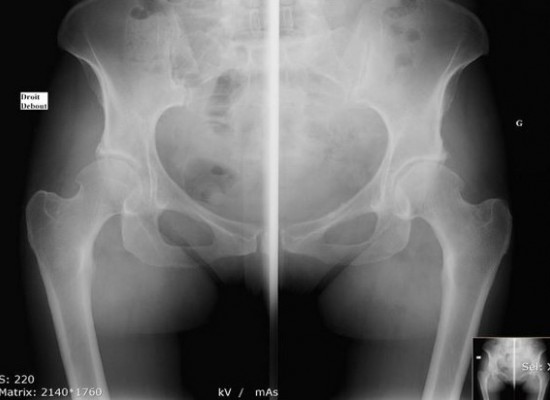

L'utilisation de la radiologie conventionnelle est facile, indolore et rapide. Elle n’est pas recommandée chez la femme enceinte. Voici les radiographies réalisées à l'ICM:

- Radiographie du squelette